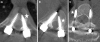

The use of thoracic pedicle screws for the treatment of adolescent idiopathic scoliosis (AIS) has gained widespread popularity. However, the placement of pedicle screws in the deformed spine poses unique challenges, and surgeons experience a learning curve. The in vivo accuracy as determined by computed tomography (CT) of placement of thoracic pedicle screws in the deformed spine as a function of surgeon experience is unknown. We undertook a retrospective review to determine the effect of surgeon experience on the accuracy of thoracic pedicle screw placement in AIS. In 2005, we started to obtain routine postoperative CT scans on patients undergoing a spinal fusion. From a database of these patients, we selected AIS patients, who underwent a posterior spinal fusion. Fifteen consecutive patients for each of the following three groups stratified by attending surgeon experience were selected (N = 45): A) less than 20 cases of all pedicle screw constructs for AIS (surgeons <2 years of practice), B) 20-50 cases (surgeons 2-5 years of practice), and C) greater than 50 cases (surgeons greater than 5 years of practice). Intraoperative evaluation of all screws included probing of the pedicle screw tract, neurophysiologic monitoring, and fluoroscopic confirmation. A total of 856 thoracic pedicle screws were studied. Postoperative CT scans were evaluated by two spine surgeons and a consensus read established as follows: (1) In: intraosseous placement or <or=2-mm breach, (2) Out: >2-mm breach, either medial or lateral. Of the 856 screws, 104 demonstrated a >2-mm breach, for an overall rate of 12.1% (medial = 55, lateral = 49, P = 0.67). When the breach rates were stratified by surgeon experience, there was a trend toward decreased rate of breach for the most experienced surgeons, although this did not attain statistical significance (Group A: 12.7%, Group B: 12.9%, Group C: 10.8%, P = 0.58). However, the most experienced group (C) had a markedly decreased rate of medial breaches (3.5 vs. 7.4% and 8.4% for groups A and B, respectively, P < 0.01). The breach rate for the concave periapical screws was not statistically different from the overall breach rate (13.0% vs. 12.1%, P = 0.93). In conclusion, the overall accuracy of placement of pedicle screws in the deformed spine was 87.9%, with no neurologic, vascular, or visceral complications. Meticulous technique allows spine surgeons with a range of surgical experience to accurately and safely place thoracic pedicle screws in the deformed spine. The most experienced surgeons demonstrated the lowest rate of medial breaches.